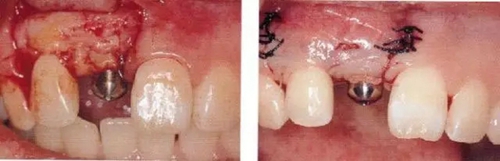

▲圖44-4,5

圖44-6

圖44-4~6 拔牙后通過骨移植材以及結(jié)締組織移植(CTG)進(jìn)行GBR。

▲圖44-7,8

7個(gè)月后,牙齦組織的愈合狀態(tài)。